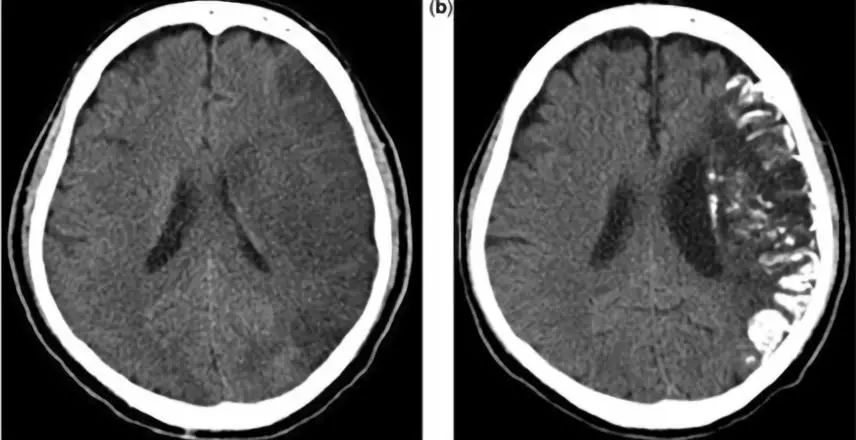

包括甲状旁腺功能减退、假性甲状旁腺功能减退、Fahr病等。这类疾病以前大家都很熟悉,甲状旁腺功能减退意味着甲状旁腺素降低,血钙降低,血磷升高,出现转移性钙化(基底节区常见)。假性甲状旁腺功能减退属于遗传性疾病,患者的甲状旁腺激素受体异常,患者临床表现和生化表现与甲状旁腺功能减退一样,但是其甲状旁腺激素是升高的。患者可伴发育异常和智力障碍,骨营养不良等。假-假性跟假性患者临床表现、影像学表现相同,但是患者生化及甲状旁腺激素全都正常。Fahr’s病多为家族遗传性,发病患者多为40~50岁,临床表现多种多样,包括神经、精神、认知等方面的异常。

1. Fahr’s病

疾病见下图。